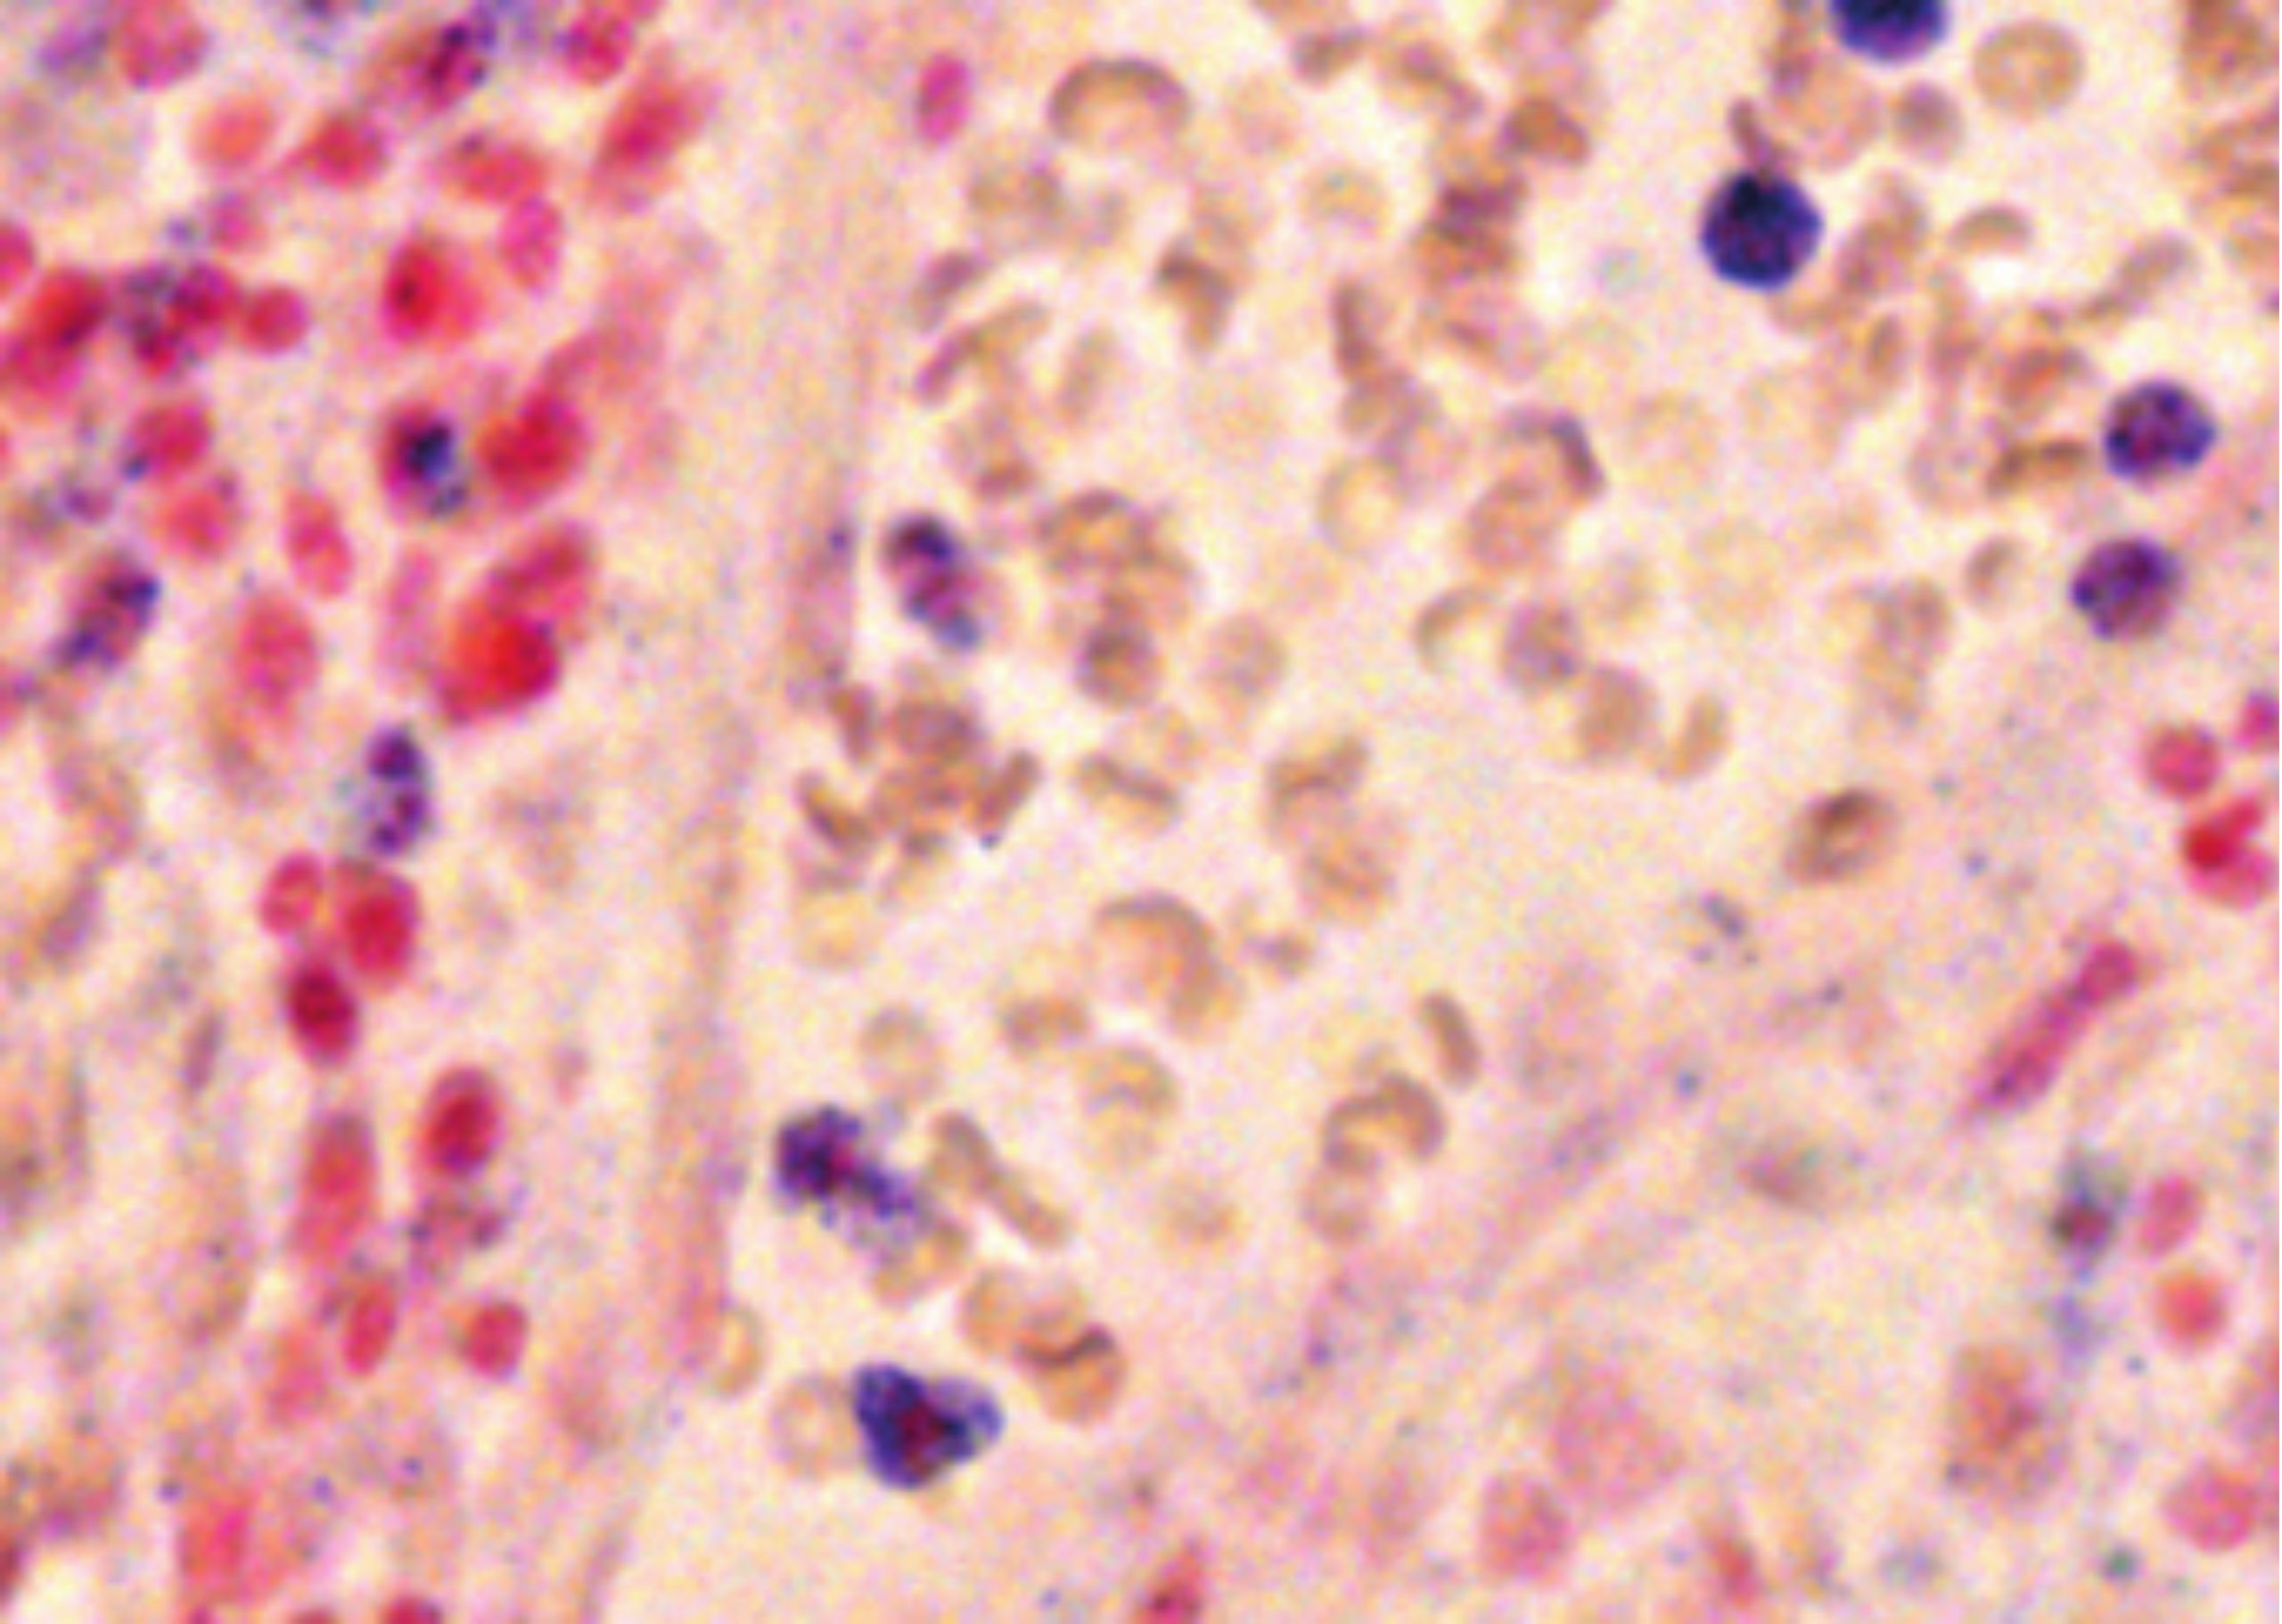

| Kit 9 | miR-223 | Myeloid, granulocytic, and monocytic compartments of the hematopoietic system | miR-223 detection in esophagus cancer |